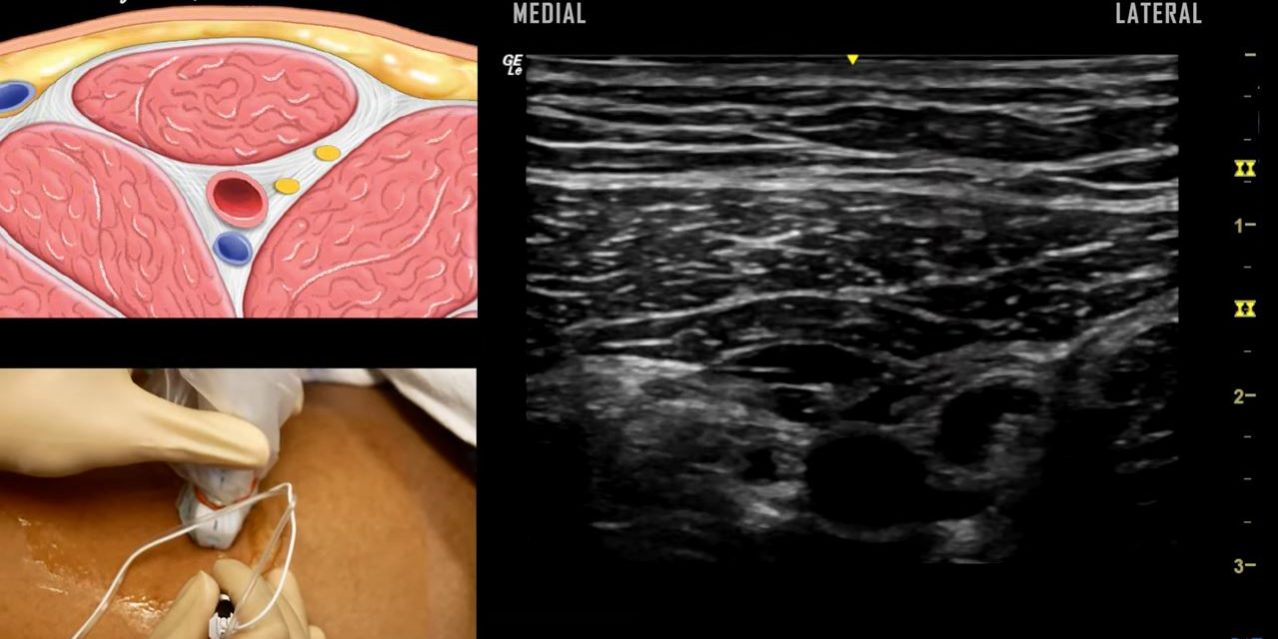

We demonstrate how to perform an in-plane approach to regional block of the saphenous nerve at the adductor canal. We review key anatomy with overlays and show injection of local anesthetic in the fascial plane. As Reddit user “anesthetica” observed, an increased angle is advised immediately prior to traversing the fascial layer to avoid inadvertent femoral artery puncture. Equipment: GE Logiq E Ultrasound Machine 22 G x 3 1/4′ (80 mm) SonoPlex echogenic stimulating needle Procedure performed by Gabrielle White-Dzuro, MD. Peer reviewed by David Hao, MD (@davidhaomd) and Raf Vazquez, MD (@RafMD1). Music “Emerald City” by Stephen Campbell, MD. Special thank you to Agung Semara Jaya for correcting our original muscle labels! — Note that the orientation of the ultrasound image may vary by institution and resource. — Disclaimer: Invasive medical procedures can result in harm to patients and practitioners and should be performed only by qualified medical professionals. This video is intended solely for informational purposes and to supplement, not replace, proper training and supervision by qualified instructors. Viewers are advised to check the most current information provided by the manufacturer for every device being used, and to verify the indications, contraindications and proper procedural technique. The dose, method of administration, and contraindications for any administered drug should be confirmed before use. The authors of the video do not assume any liability for any injury or damage to any person or property arising from the use of this video.